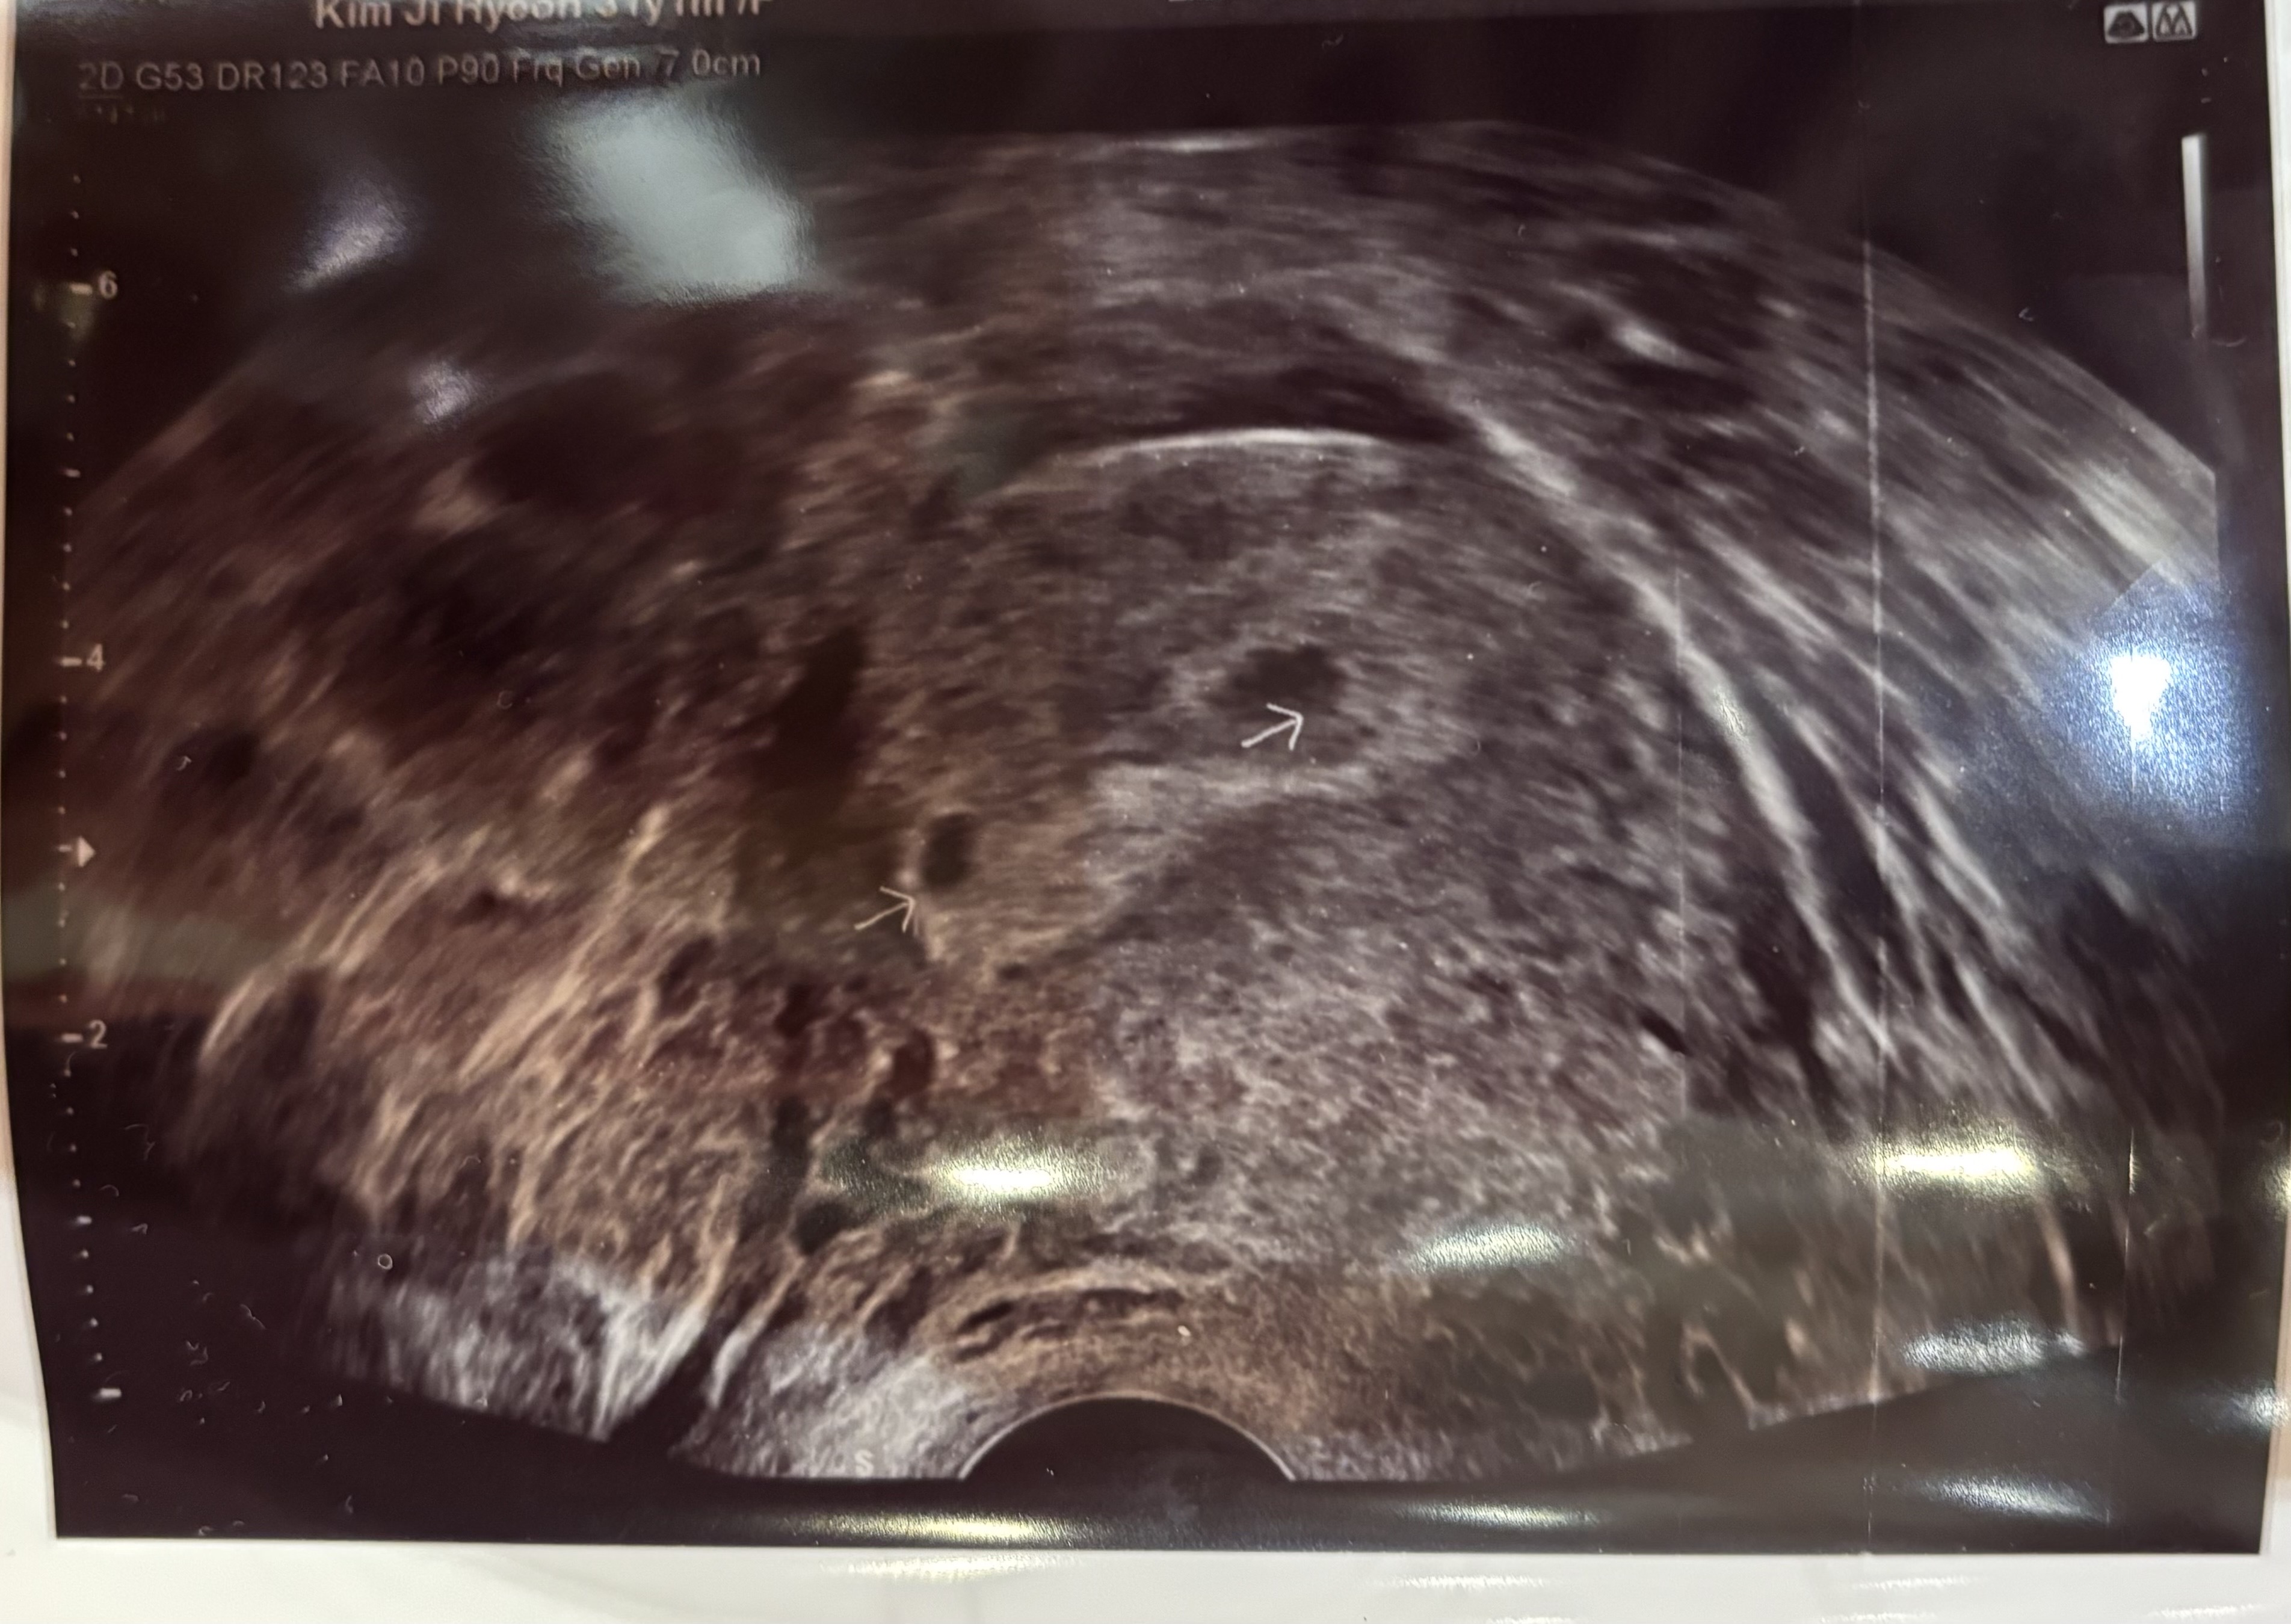

아직 난황은 못봤지만 아기집이 두개 보인다고 하시는데 쌍둥이일까요...? 하나는 흡수되어 없어질수있다고는 하셨는데....